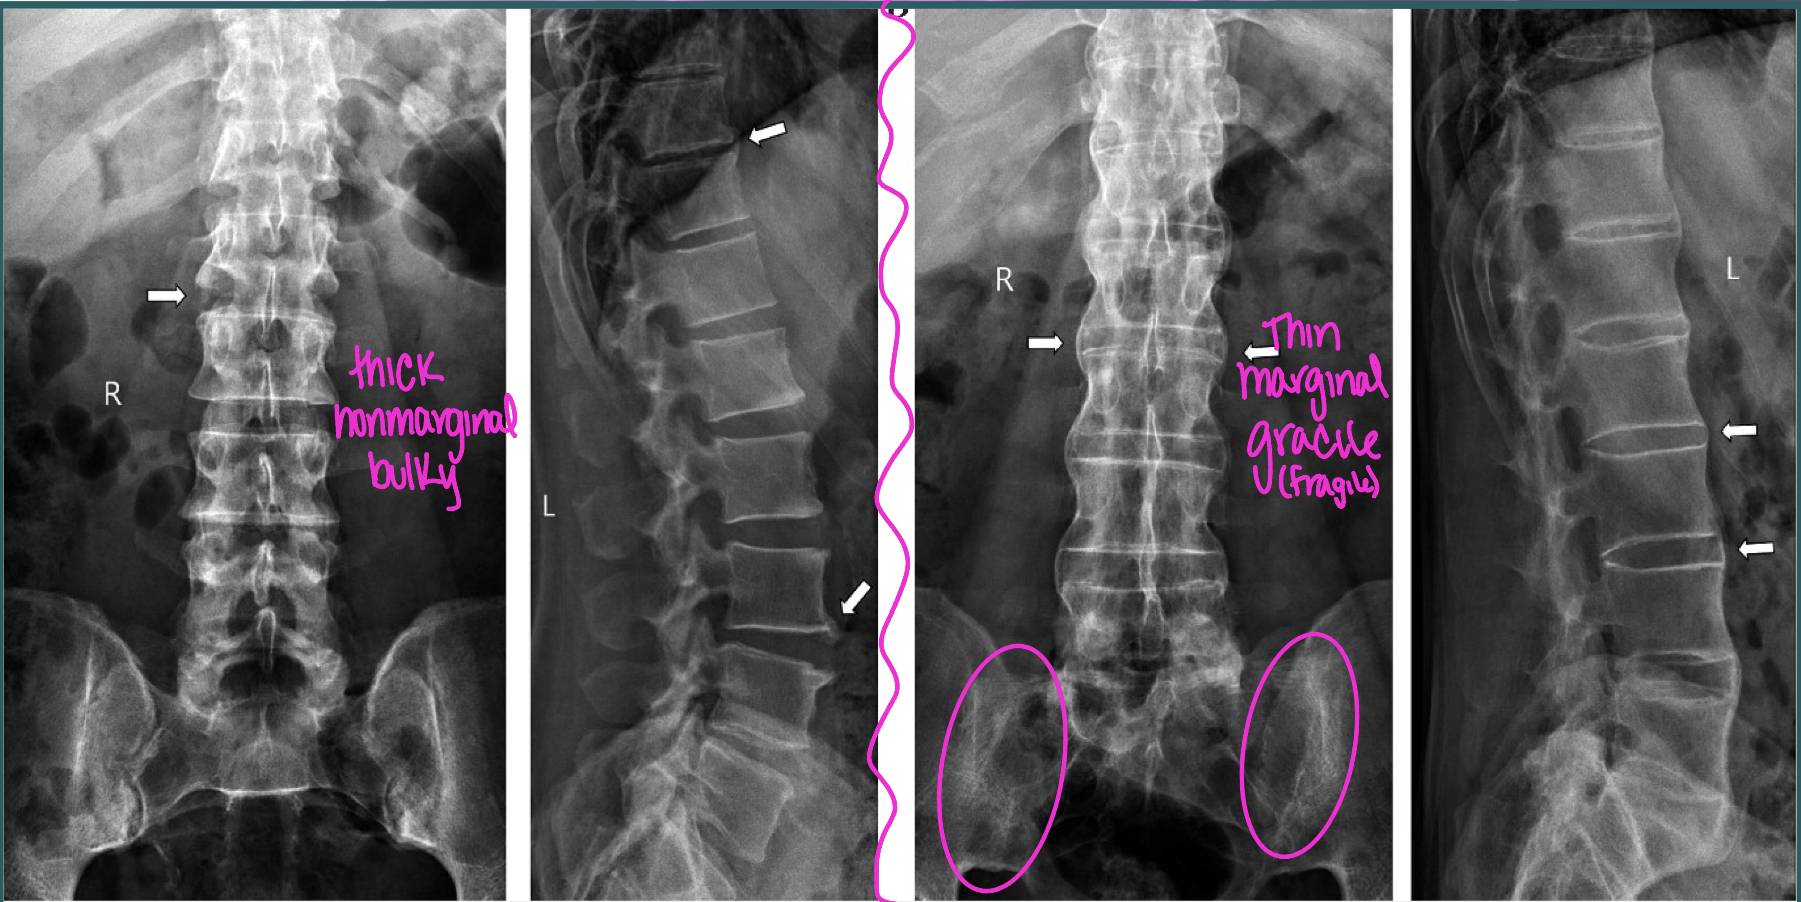

What two findings of AS are found in this image

Corner erosions (Romanus lesions)

Reactive sclerosis (shiny corner)

Loss of anterior concavity (vertebrae squaring)

What finding of AS is found in this image

symmetrical, thin, marginal syndesmophytes (bamboo sign)

gracile/fragile

AS and Enteropathic arthritis syndesmophyte characteristics

symmetrical, thin, gracile/fragile marginal

asymmetrical, thick, bulky nonmarginal (above and below endplates)